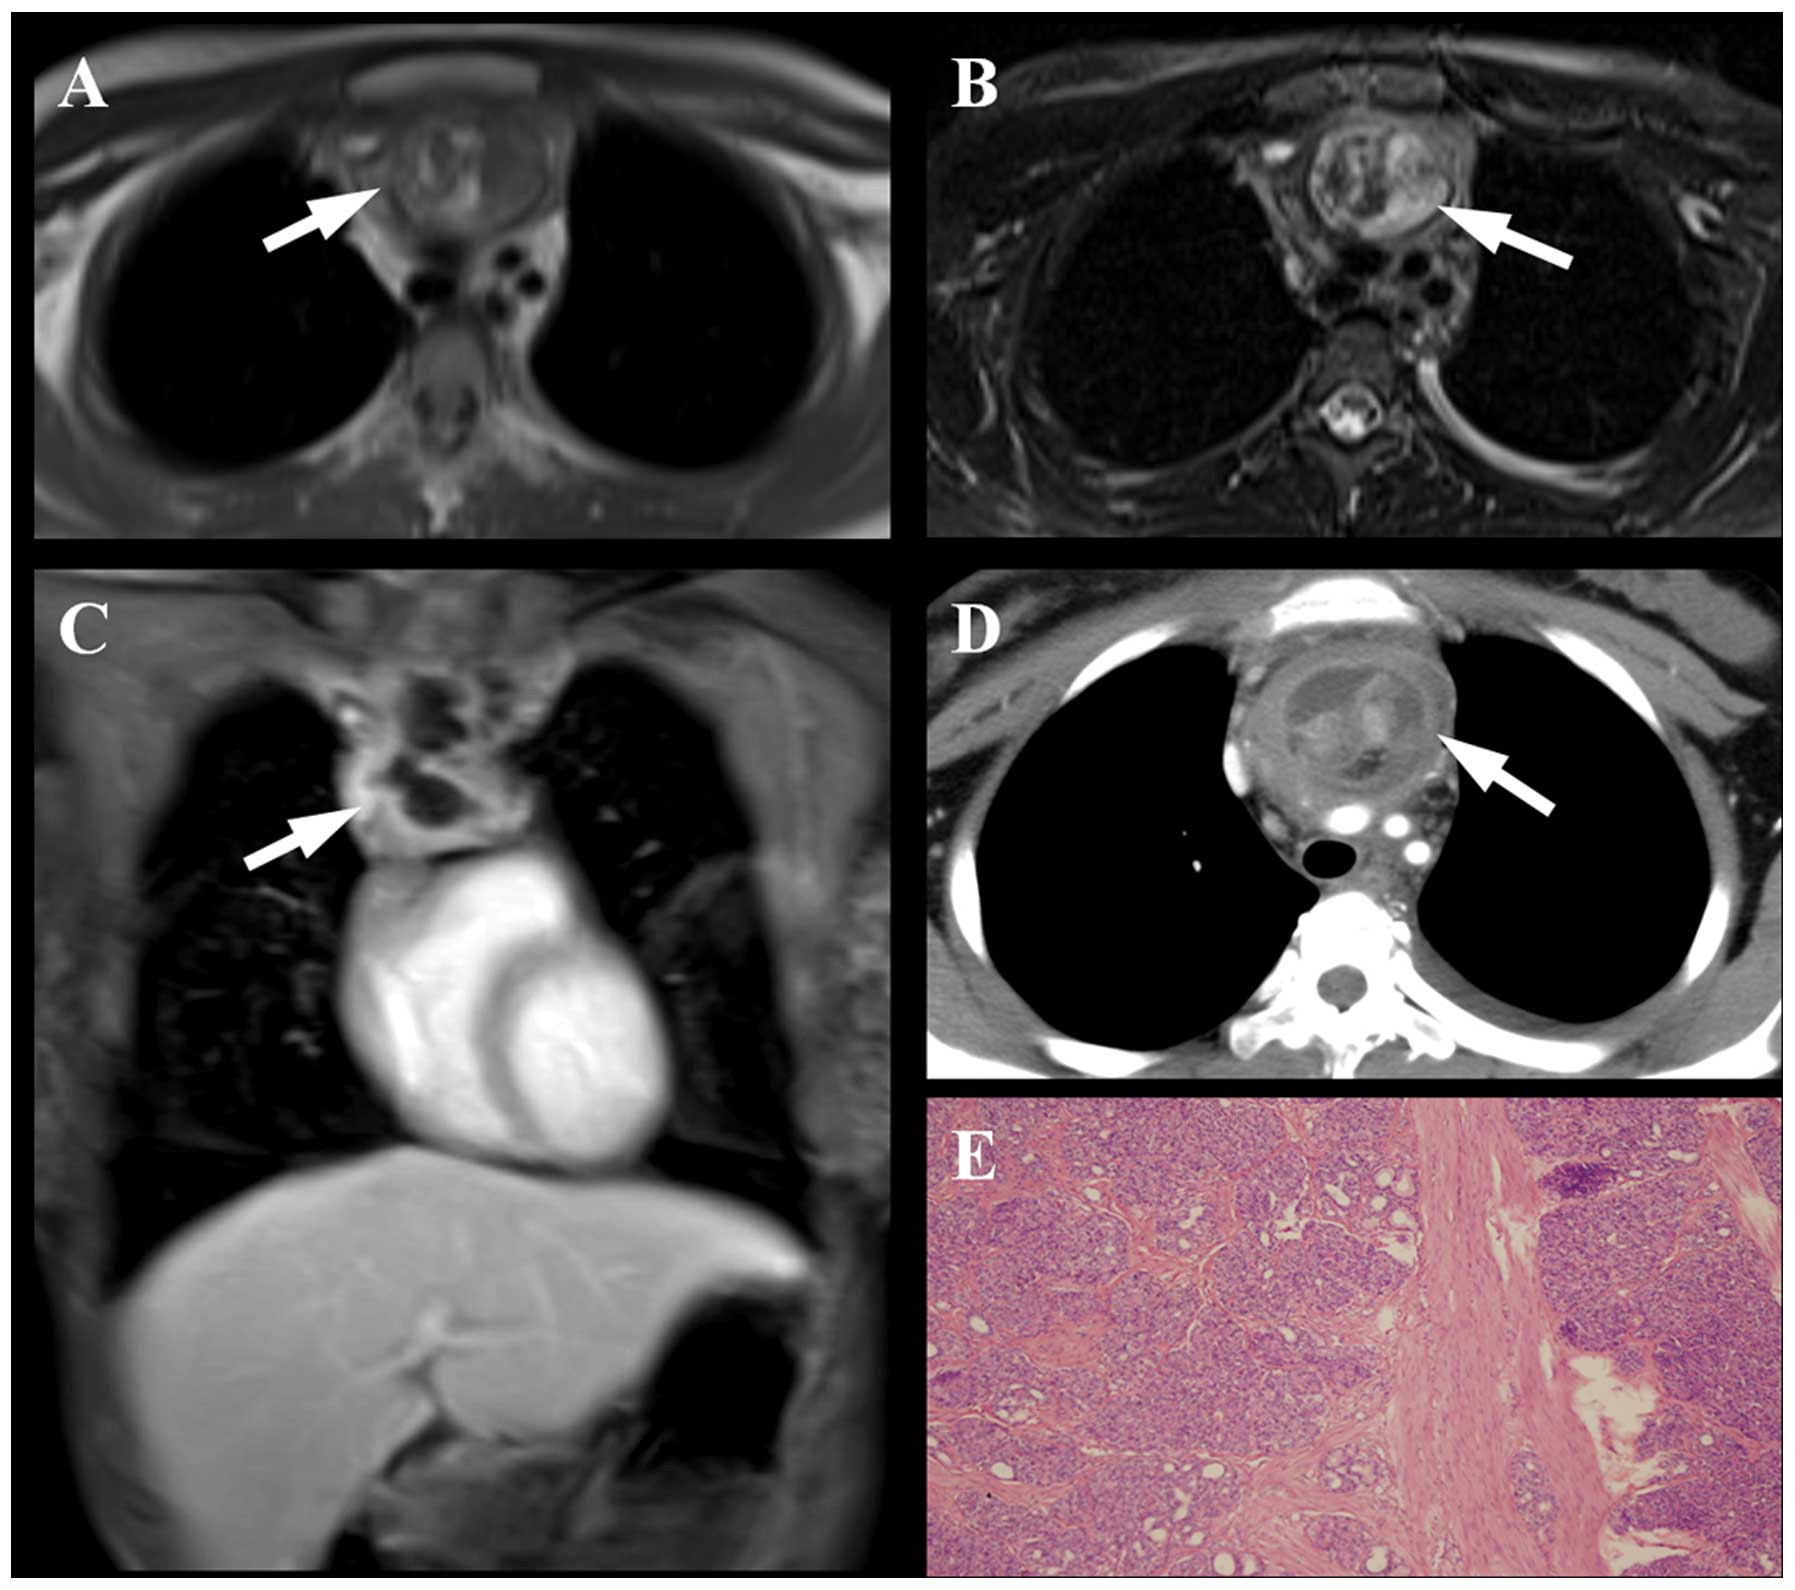

Ectopia of the pancreatic tissue is a developmental anomaly found in ~2% of all autopsies, and 70~90% of these anomalies are located in the gastrointestinal tract. Mediastinal localization of an ectopic pancreas is extremely rare. Herein, we report two cases with mediastinal ectopic pancreas clarified by pathology and shown by thoracic contrast‑enhanced computed tomography (CT) and magnetic resonance imaging (MRI). In addition, a brief review of the relevant literatures is presented. Although CT and MRI manifestations of this lesion are nonspecific, certain notable findings need to be focused on. When there is a mass in the anterior mediastinum with marked and heterogeneous enhancement, along with necrotic and liquefied non‑enhanced areas in the center, ectopic pancreas should be considered and differentiated from other neoplasms in this region.

Figure 1

Figure 2